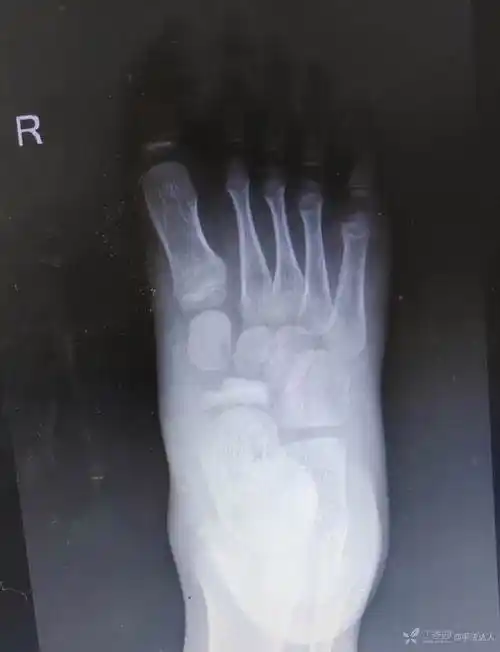

男6岁足舟骨坏死无外伤史怎么诊断怎么处理